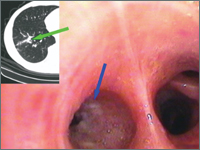

Obustronne guzy płuc - co robić?

Bilateral lung tumors - what to do?

Internal MedicineTumors were detected in a 59-year-old male long-term smoker with no significant past medical history of both lungs. A bronchoscopy was performed, which showed bronchial stenosis on the right side to segment 9 by a submucosal infiltration. Cytological examination of the brush biopsy smear and histopathological examination of the sections from the lesion yielded a diagnosis of squamous cell carcinoma. Due to the equivocal nature of the left lung lesion on CT scan, a PET-CT was performed. The result of the study: SUVmax of right lung cancer = 1.9; left lung tumor = 8.8.It was decided to perform thoracotomy left-sided thoracotomy. An ad hoc intraoperative cytological examination of the left lung tumor impression revealed non-small cell carcinoma cells. The lower lobe was removed along with the mediastinal lymph nodes. After two months, a video-guided right lower lobectomy with mediastinal lymphadenectomy was performed. Histopathological examination of the right lung revealed pre-invasive squamous cell carcinoma while the left lung was diagnosed as squamous cell carcinoma with an intermediate grade of cell differentiation (G2). Taking into account the criteria of Martini and Melamed, bilateral synchronous foci of of primary cancer.